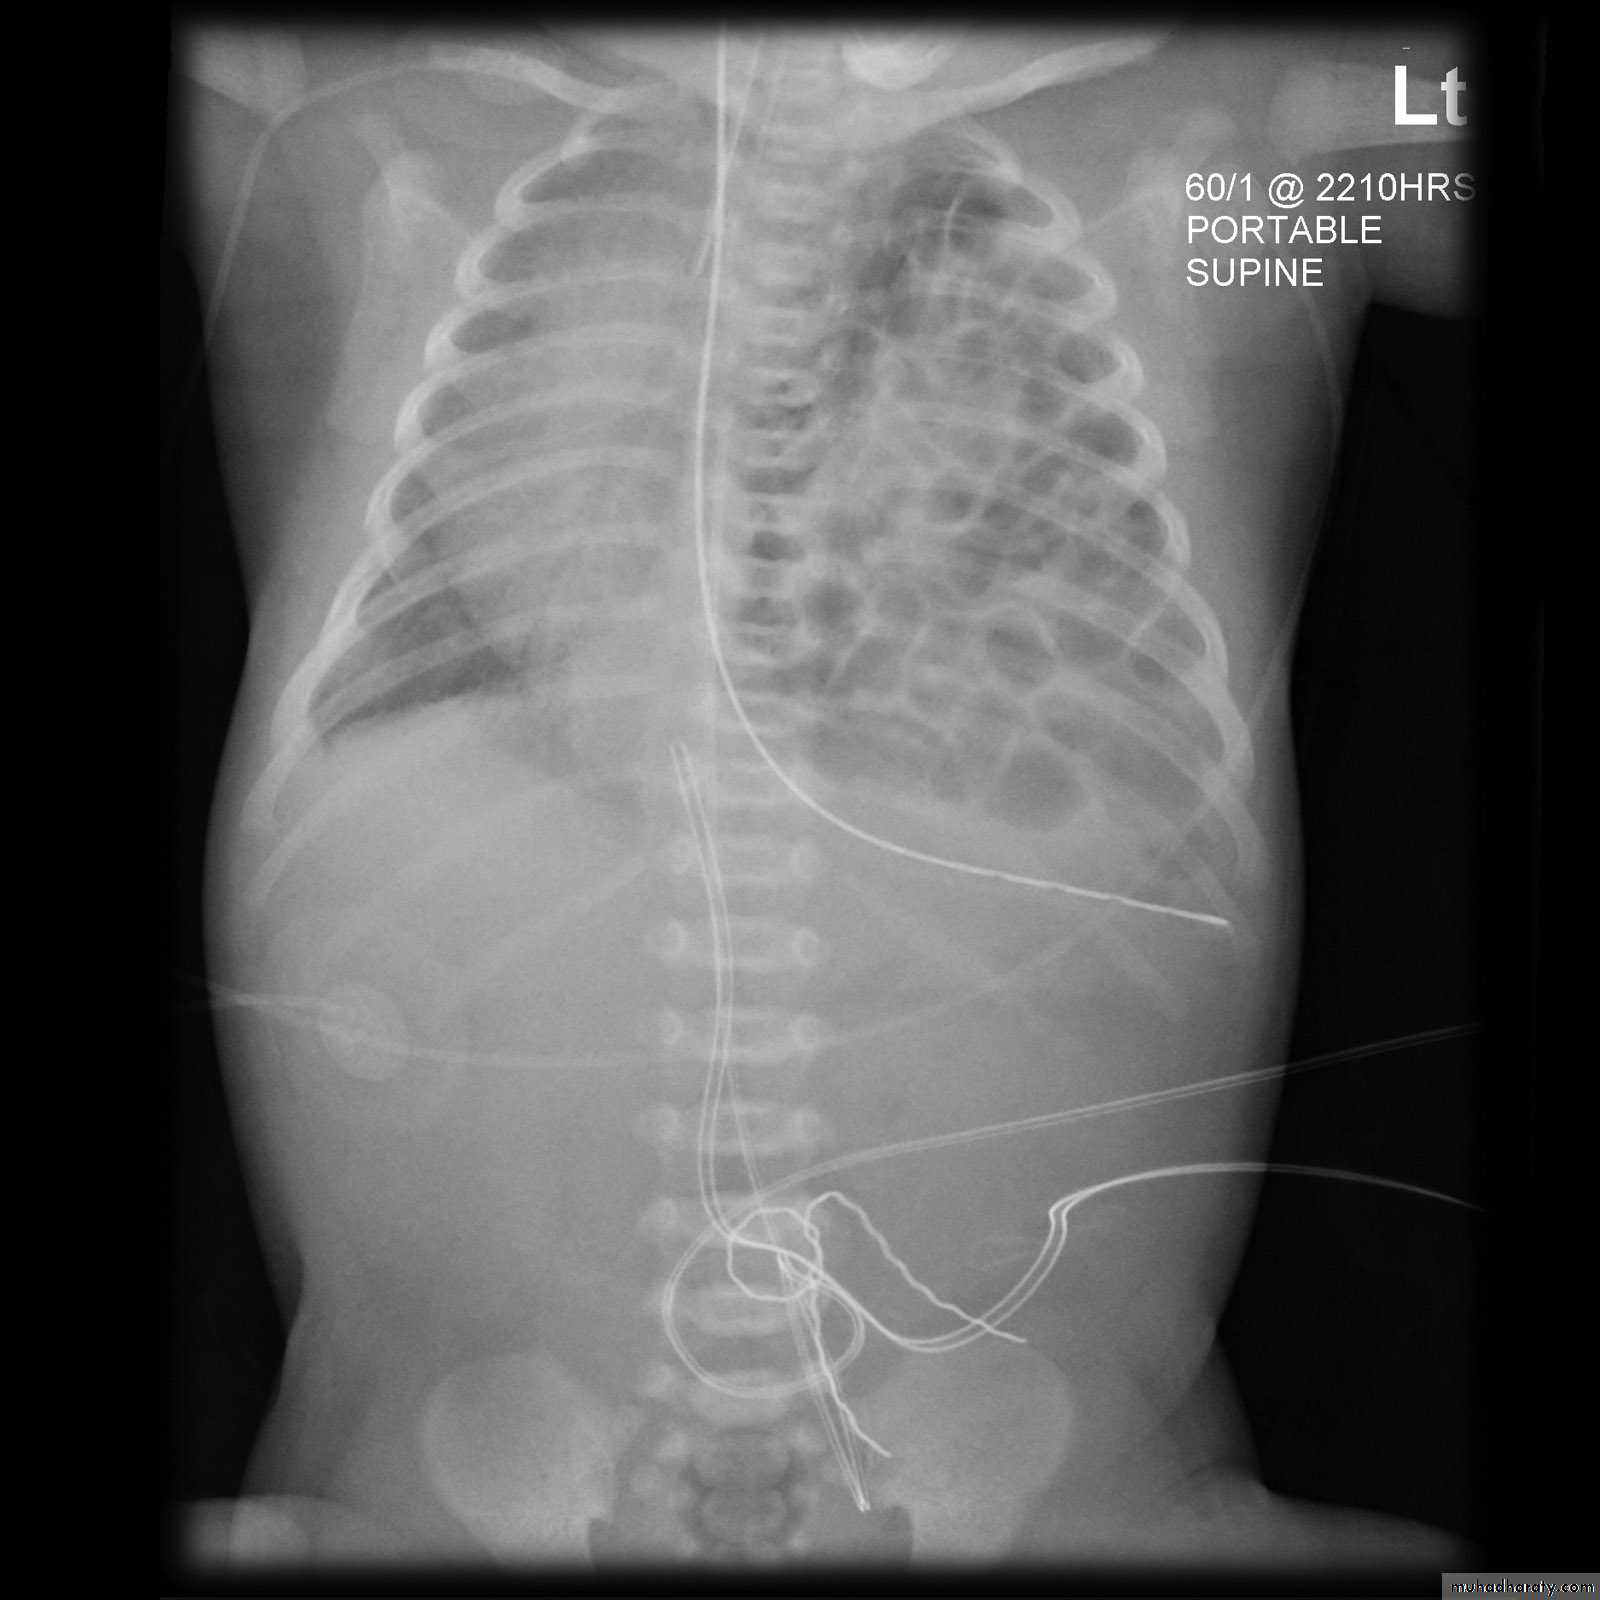

Tension pneumothorax

56.tension pneumothorax left sided aspect

57. tension pneumothorax right sided aspect